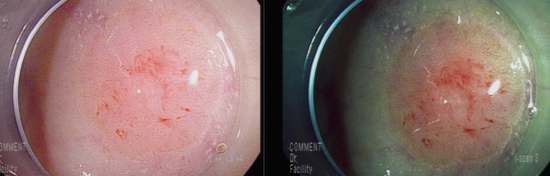

직장에 일부 출혈을 보이는 Vn pit pattern, 중심부 미란성 소견을 동반한 8 mm 크기의 용종 관찰됨.

점막암 이상의 병변을 의심하여 충분히 융기시킨 후 근위부에 snare를 anchor할 hole을 만든 후 충분히 잡아서 육안적 완전 절제함